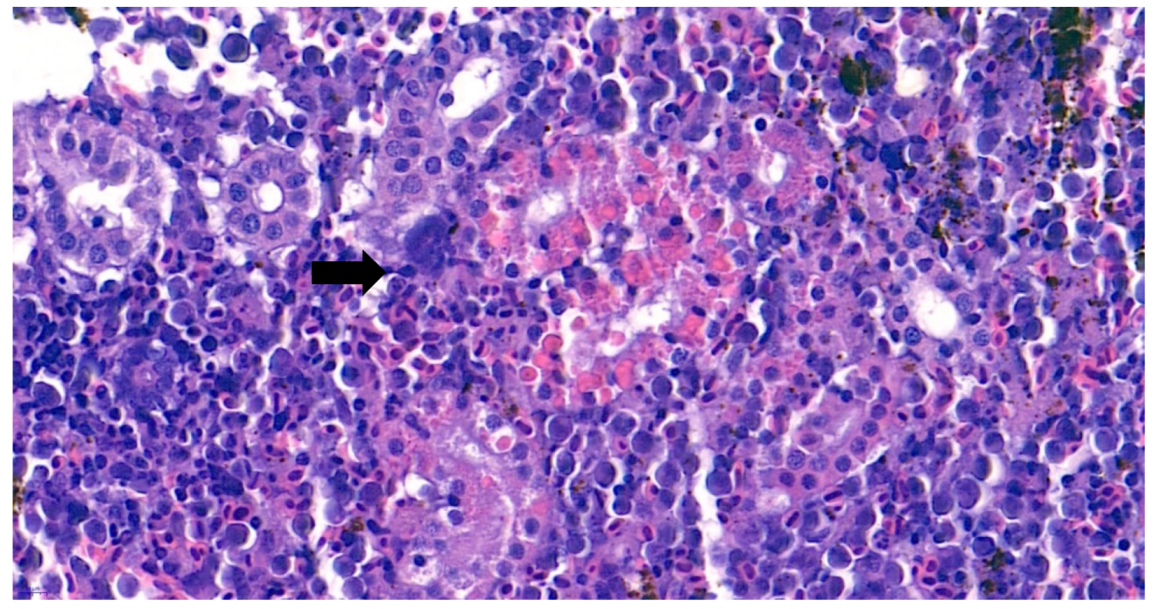

3.3. Histopathological Analysis